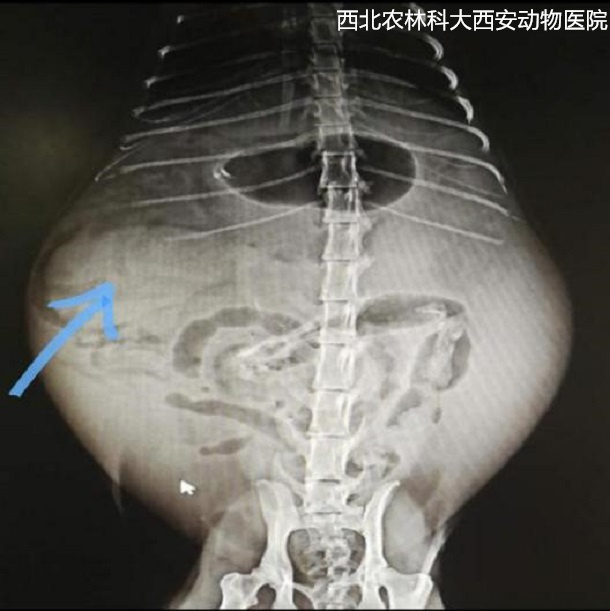

輔助檢查:腹部平片顯示腹腔有一中等密度占位性病變位于左下腹部,腹部器官邊緣銳利程度消失,腹部影像漿膜細(xì)節(jié)不能清晰可見(jiàn),胃和部分腸管積氣,提示腹腔積液、疑似占位待查見(jiàn)(圖1)。為進(jìn)一步診斷腹部占位的性質(zhì),對(duì)患寵進(jìn)行了超聲檢查,結(jié)果顯示腹腔間隙無(wú)回聲,腸管游離,腹腔肝后至膀胱有一非均質(zhì)、低回聲腫物,邊緣圓鈍,輪廓清晰,腫物內(nèi)部偶見(jiàn)低回聲病灶。提示腹腔積液、脾腫大且結(jié)構(gòu)異常,未見(jiàn)扭轉(zhuǎn),待查見(jiàn)(圖2)。

圖一